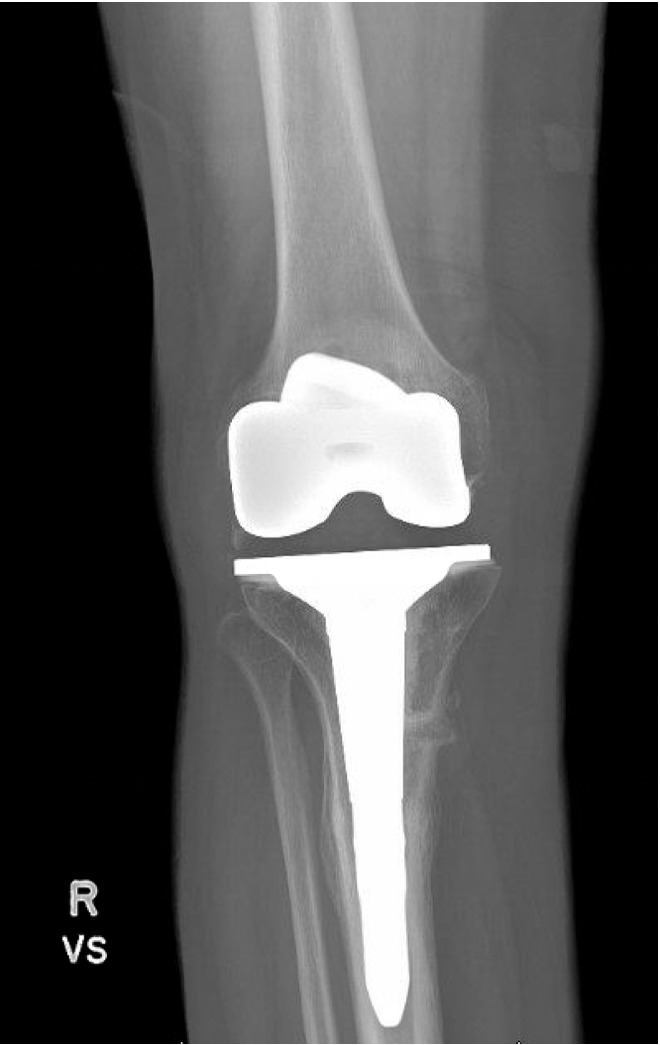

The total estimated blood loss was 300 mL, and no transfusion was required. The patient tolerated oral intake on the evening of surgery, completed her first physiotherapy session the following morning, and ambulated fifty feet with a rolling walker while wearing the hinged knee brace locked in extension. Following ambulation, full length lower extremity films were re-obtained, demonstrating neutral mechanical hip–knee–ankle axis (Figure 5). She was discharged home on post-operative day two with acceptable pain control and an incision that was clean, dry, and intact.

Quantitative range-of-motion and outcome-score data are summarized in Table 1. At the two-week clinic visit the incision was fully healed and sutures were removed. The patient continued full weight bearing in the brace. By six weeks the osteotomy displayed bridging callus across the osteotomy site (Figure 6), the brace was discontinued, and she achieved an unrestricted gait pattern without assistive devices. Four months after surgery, the patient had resumed activities such as tennis and reported no pain or swelling. Radiographs at that time demonstrated complete cortical union without any interval changes in alignment (Figure 7). At the nine-month assessment she reported hiking up to five miles and skiing on groomed slopes without limitation. Imaging showed continued consolidation of the osteotomy and stable components (Figure 8).